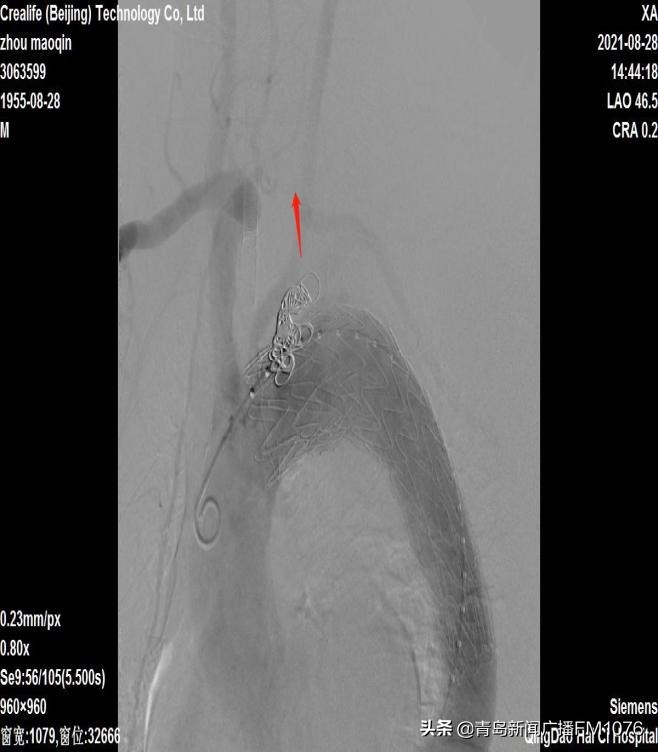

手术先进行左颈总动脉-左锁骨下动脉人工血管转流术,保证脑部和上肢的血液供应。后于采用微创介入手术方式,于右股动脉穿刺入路行主动脉弓动脉瘤腔内隔绝术,术中造影见转瘤人工血管血流通畅,主动脉弓动脉瘤封堵良好,未见内漏。既保证了脑部及上肢的血供,又完全腔内隔绝了主动脉弓动脉瘤,从而保证肿瘤不会破裂和生长,安全解除了患者体内的“定时*弹炸**”。杂交手术历时3.5小时成功完成,术后一天,患者恢复良好转回普通病房,目前已康复出院。

转流人工血管

红色箭头为转流人工血管